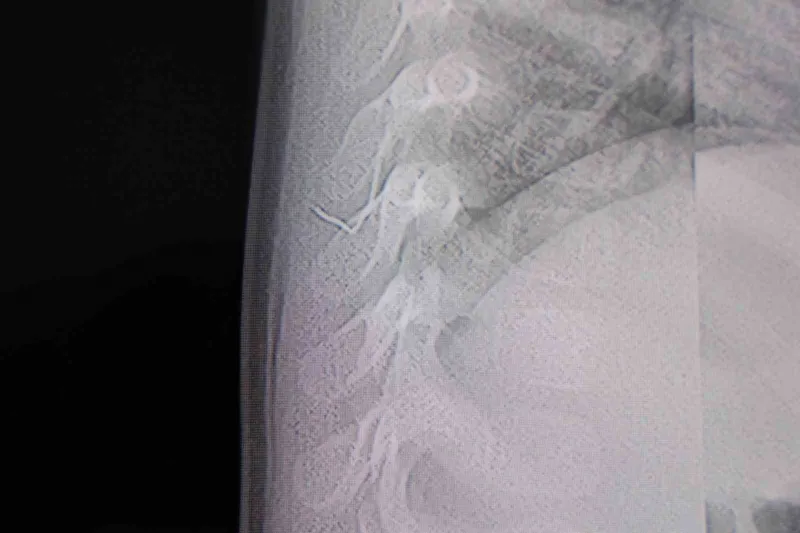

Kahramanmaraş’ta sırt üstü yatmak istemeyen, yatırıldığında ağlama ve huzursuzluğu nedeniyle hastaneye götürülen bir yaşındaki bebeğin sırtından akciğer zarına doğru ilerleyen 2 santimetrelik zımba teli çıktı.

Alınan bilgiye göre, Kahramanmaraş’ta farklı ortopedi, çocuk cerrahisi ve beyin cerrahisi kliniklerine başvurusu yapılan bir yaşındaki bebeğin, sırt bölgesinde yabancı bir cisim olduğu ancak müdahalenin zor olduğu ve 8 yaşına kadar beklenmesi gerektiği bildirildi. Aile, bebekleri için son olarak HG Hospital’e başvurdu. HG Hospital Beyin ve Sinir Cerrahisi Uzmanı Prof. Dr. İdris Altun tarafından yapılan tetkiklerde, yabancı cismin cilt altında, omurilik kanalına yakın bir bölgede olduğu ve akciğer zarına doğru ilerlediği belirlendi. Hasta, genel anesteziye alınmadan, lokal anestezi ve sedasyon eşliğinde ameliyata alındı. Yapılan müdahalede yabancı cisim tamamen çıkarıldı. Çıkarılan cismin, ince zımba teline benzer metal bir tel olduğu ve yaklaşık 2 santimetre uzunluğunda bulunduğu tespit edildi. Hasta, aynı gün taburcu edildi.

Konuya ilişkin açıklama yapan Prof. Dr. İdris Altun, "Sırtında yabancı bir cisim olduğu söylenmiş ancak çıkarılamayacağı ve 8 yaşına kadar beklenmesi gerektiği ifade edilmişti. Bize başvurduğunda yaptığımız tetkiklerde, cilt altında, omurilik kanalına çok yakın ve akciğer zarına doğru ilerleyen bir yabancı cisim tespit ettik. Hastamızı tamamen uyutmadan, lokal anestezi ve sedasyon eşliğinde müdahale ederek lezyonu tamamen çıkardık. Çıkardığımız cismin ince zımba teline benzer, yaklaşık 2 santimetre uzunluğunda metal bir tel olduğunu gördük. Bu yabancı cisim alınmasaydı, bölgede enfeksiyon gelişebilirdi. Enfeksiyon sonucu omurilik kanalında ciddi hasarlar oluşabilir, çocuk büyüdükçe cismin hareket etmesine bağlı olarak omurilikte zedelenmeler meydana gelebilirdi. Ayrıca yana doğru ilerleyerek akciğer zarına ve akciğere batma riski vardı. Bu da enfeksiyona ve ilerleyen süreçte tümörle karışabilecek tablolara neden olabilirdi. Şu an hastamız gayet sağlıklı. Gerekli kontrolleri yaptık ve aynı gün taburcu ettik" dedi.